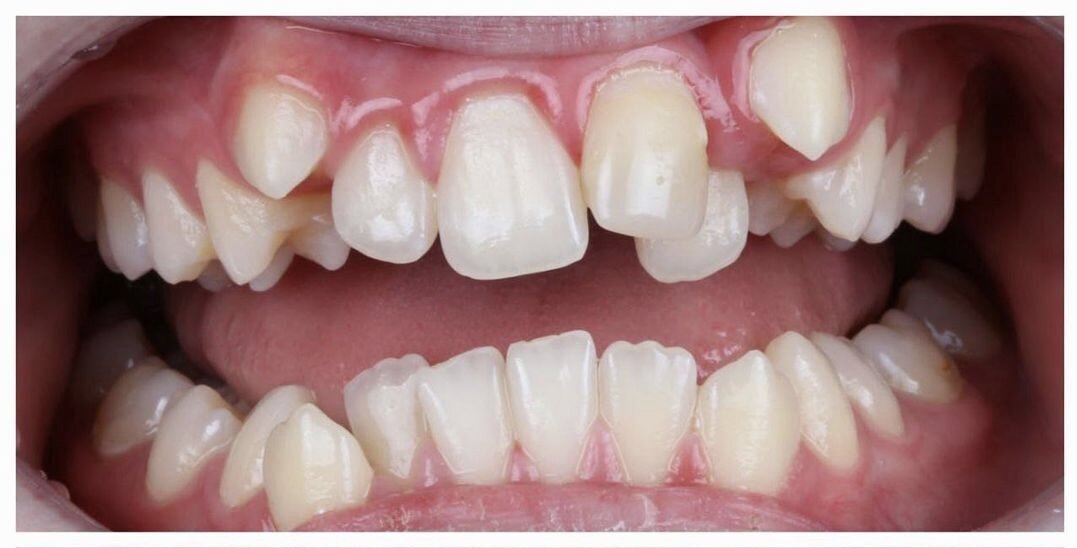

К нам в клинику обратился пациент в возрасте 14 лет с большим дефицитом места на верхней челюсти. Как часто при этом бывает - скученность зубов и клыки располагаются вне зубного ряда.

Исходная ситуация до ортодонтического лечения

• Можно просто выровнять зубы? Тогда мы получим наклон зубов и корни зубов выйдут из костной ткани. Сразу это не заметно, но спустя годы начнётся осложнение - оголение десны. А значит, нельзя.

• Можно провести ортодонтическое лечение с удалением премоляров, чтобы создать необходимое место для расположения зубов? Можно! Но так не хотелось бы удалять.